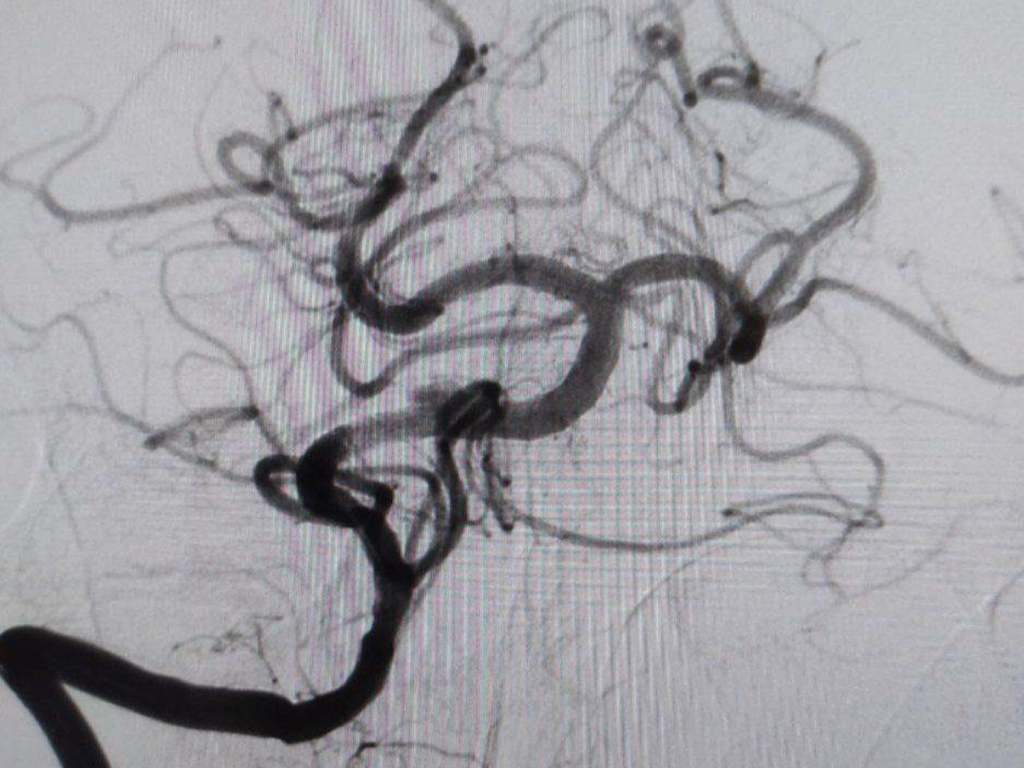

Как рассказали медики, у мужчины не было типичных признаков инсульта — паралича или проблем с речью. Ночью он просто почувствовал головокружение и тошноту, а утром обнаружил, что не может встать. Бригада скорой помощи доставила его в Региональный сосудистый центр, где врачи диагностировали закупорку основной артерии, обеспечивающей кровоснабжение важнейших отделов головного мозга.

Пациенту экстренно провели операцию — удалили тромб и установили стент.